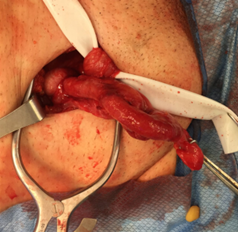

Q7. An intraoperative image of an inguinal hernia is shown. Which type is depicted?

- Littre

- Amyand

- Garengeot

- Grynfelt

Answer – B